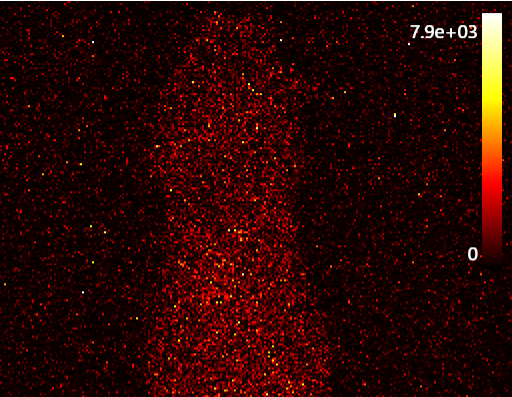

Autoluminescent noise observed with the PRISM In Vivo Imaging System

Despite the high cost, cooled CCD cameras are still often considered the gold standard by researchers, underscoring the need for more cost-effective alternatives. Although cooled CCD cameras are still treated as the reference point in preclinical imaging, their expense and outdated design limit broader adoption. Using our NIST-calibrated light source, we validated the PRISM BIO-BOX powered by a Sony CMOS sensor, which has already shown sensitivity down to ~3,000 photons/s/cm²/sr. Until now, the lack of a traceable calibration tool has made it difficult to fairly make such comparisons.